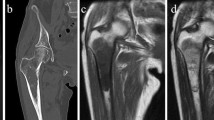

USZ20-EMC1: A 54-year-old female patient initially presented in 2009 with a mass in her knee para-patellar medial right and was diagnosed with an extraskeletal myxoid chondrosarcoma (EMC). After several resections from loco-regional recurrences, the patient underwent an amputation of her lower leg in late 2020 and the USZ20-EMC1 cell model was established from fresh material. The patient is currently suffering from metastatic disease to the lung. Lung metastases were continuously treated with surgical resection, radiation therapy and cryoablation. The USZ22-EMC2 cell model was established from a diagnostic biopsy specimen of a 68 year old male patient that presented with a 13 cm mass in the left thigh. The present study was conducted following regional/cantonal and institutional guidelines and in compliance with the Helsinki Declaration and after approval by our cantonal ethical review board Zurich (BASEC-2021–00,417).

We established two novel ex vivo sarco-sphere cell models from two patients diagnosed with an EMC. USZ20-EMC1 was established from an amputation specimen from a 54 year old patient with a long history of recurrent and metastatic EMC and USZ22-EMC2 was established from a fresh biopsy taken from a left thigh mass of a 68 year old patient at the time of diagnosis (Fig. 1a, b). USZ20-EMC1 and USZ22-EMC2 cells were cultured in 3D as sarco-spheres for more than 24 passages over 12 months and more than 8 passages over 6 months, respectively (Fig. 2b, f). Cells were biobanked in our living biobank in the Department of Pathology and Molecular Pathology, University Hospital Zurich, Switzerland. Both models were also able to attach and grow on collagen coated plates as monolayer cultures (2D) (Fig. 2a, e). Phenotypic analysis showed that the morphology of the sarco-sphere models recapitulated the native tumor tissue (Fig. 2c, d, g, h). Inference of their cell growth indicated a doubling time of 5.09 days for USZ20-EMC1 and 6.05 days for USZ22-EMC2 (Fig. 3a, b).

Bright field images show cells attached as a monolayer culture in 2D for USZ20-EMC1 (A) and for USZ22-EMC2 (E) and grown as sarco-spheres in 3D for USZ20-EMC1 (B) and for USZ22-EMC2 (F). Hematoxylin and Eosin stains show in the native tumor tissue (C, G) cells that are embedded in an abundant pale-blue myxoid or chondromyxoide matrix. The cells themselves have a deeply eosinophilic cytoplasm, as well as uniform round to oval nuclei. Corresponding cell morphology is seen in the histology from the sarcosphere models native tumor and correscponsing organoids (D, H). C + D are representing tissue and sarco sphere from USZ20-ECM1 and G + H are representing tissue and sarco sphere from USZ22-ECM2. Scale bars indicate 50 µM in C, D, G and H, 100 µM in A, B, E and F